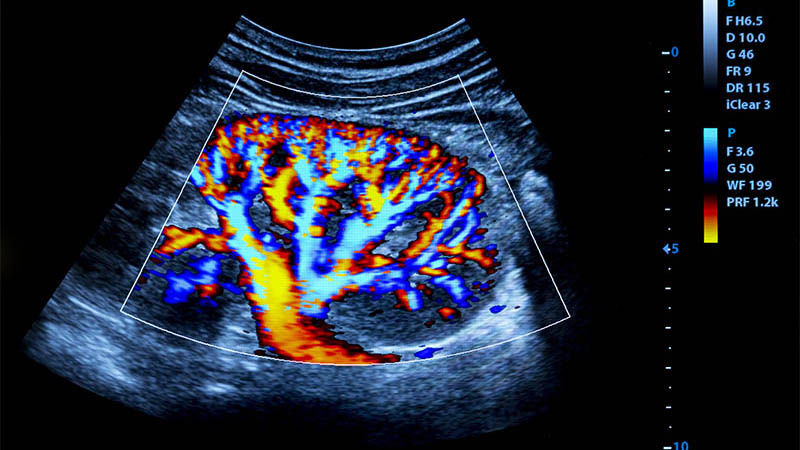

3D ultrasound of fetal congenital heart disease: findings from virtual and physical models

Caroline Oliveira Nieblas, Edward Araujo Júnior, Nathalie Jeanne Magioli Bravo-Valenzuela, Marcela Castro Giffoni, Maria Fátima Pereira Leite, Heron Werner

J Ultrason 2025; 25: 26